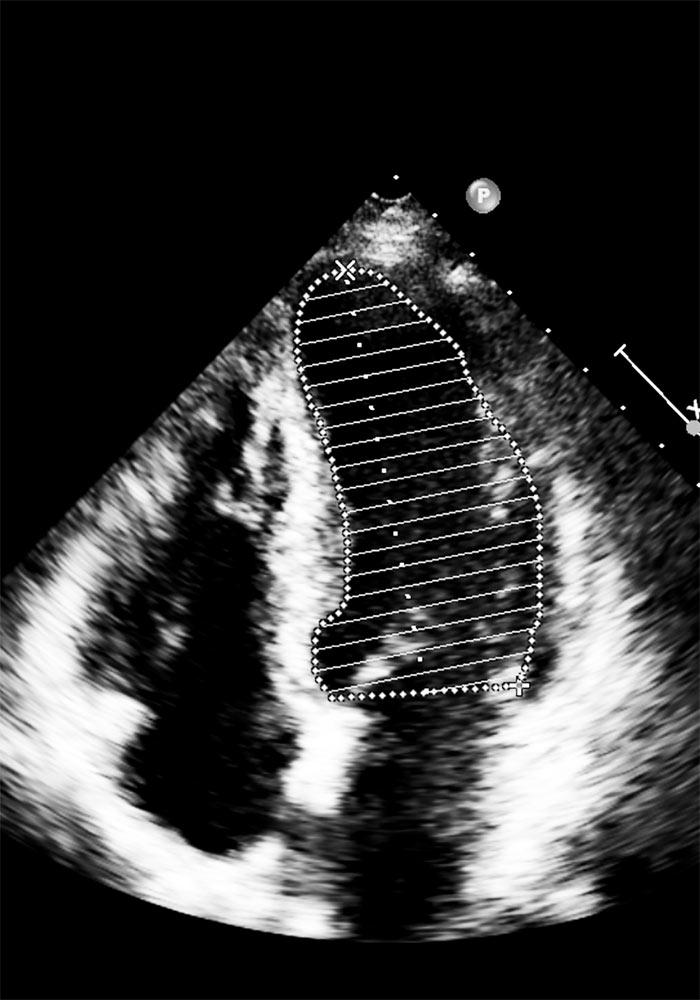

- Εκτίμηση της καρδιακής λειτουργίας: Η εξαγωγή ποσοστών όπως το κλάσμα εξώθησης μπορεί να δείξει πόσο αποτελεσματικά η καρδιά αντλεί αίμα.

- Δομικές ανωμαλίες: Ο εντοπισμός ατελειών στον καρδιακό μυ ή τις βαλβίδες μπορεί να προσφέρει στοιχεία για πιθανά καρδιολογικά νοσήματα.

- Προβλήματα στη ροή του αίματος: Αποκλίσεις στη ροή μπορεί να δείξουν απόφραξη ή άλλες παθολογικές καταστάσεις.

Οι ιατροί εξετάζουν προσεκτικά τις εικόνες που προκύπτουν από το υπερηχογράφημα για να διαμορφώσουν μια συνολική εικόνα της υγείας της καρδιάς του ασθενούς. Επίσης, είναι σημαντική η παρακολούθηση τυχόν αλλαγών με την πάροδο του χρόνου. Οι παράγοντες που ληφθούν υπόψη περιλαμβάνουν: